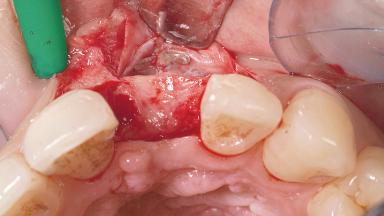

Late Placement of an Implant in a Maxillary Left Central Incisor Site

A 30-year-old female patient had lost tooth 21 and was referred to our clinic for consultation and treatment. Due to advanced apical infection, tooth 21 had been extracted two months earlier at another clinic and an acrylic-resin tooth had been bonded to the adjacent teeth. The patient desired implant treatment to avoid any damage to the adjacent natural teeth. While the patient had no history of any systemic disorder, she was a heavy smoker and exhibited medium to advanced periodontitis in the entire jaw. After the initial treatment to achieve a pocket probing depth of less than 4 mm and no bleeding on probing, a decrease in the height of the papillae mesial and distal to the extraction site and overall gingival recession were observed.

| Bone Augmentation | Horizontal|Staged |

| Augmentation Materials | Autogenous chips|Membrane |

| Soft Tissue Grafting | Simultaneous |